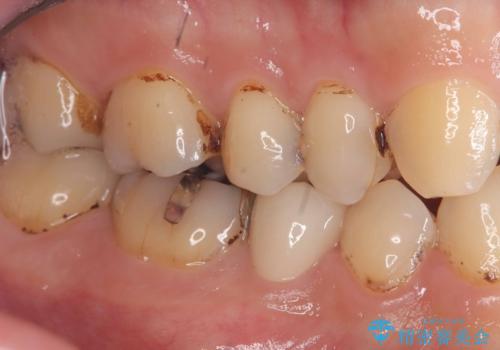

- 虫歯が大きく歯が欠けている状態でした。 そこに食べ物も詰まっている状態でした。

虫歯を除去後、精密根管治療を行い、オールセラミッククラウンで治療を行いました。

虫歯が大きく神経まで到達していました。将来根尖性歯周炎にならないよう徹底的に神経をとり洗浄したうえで被せ物をしています。